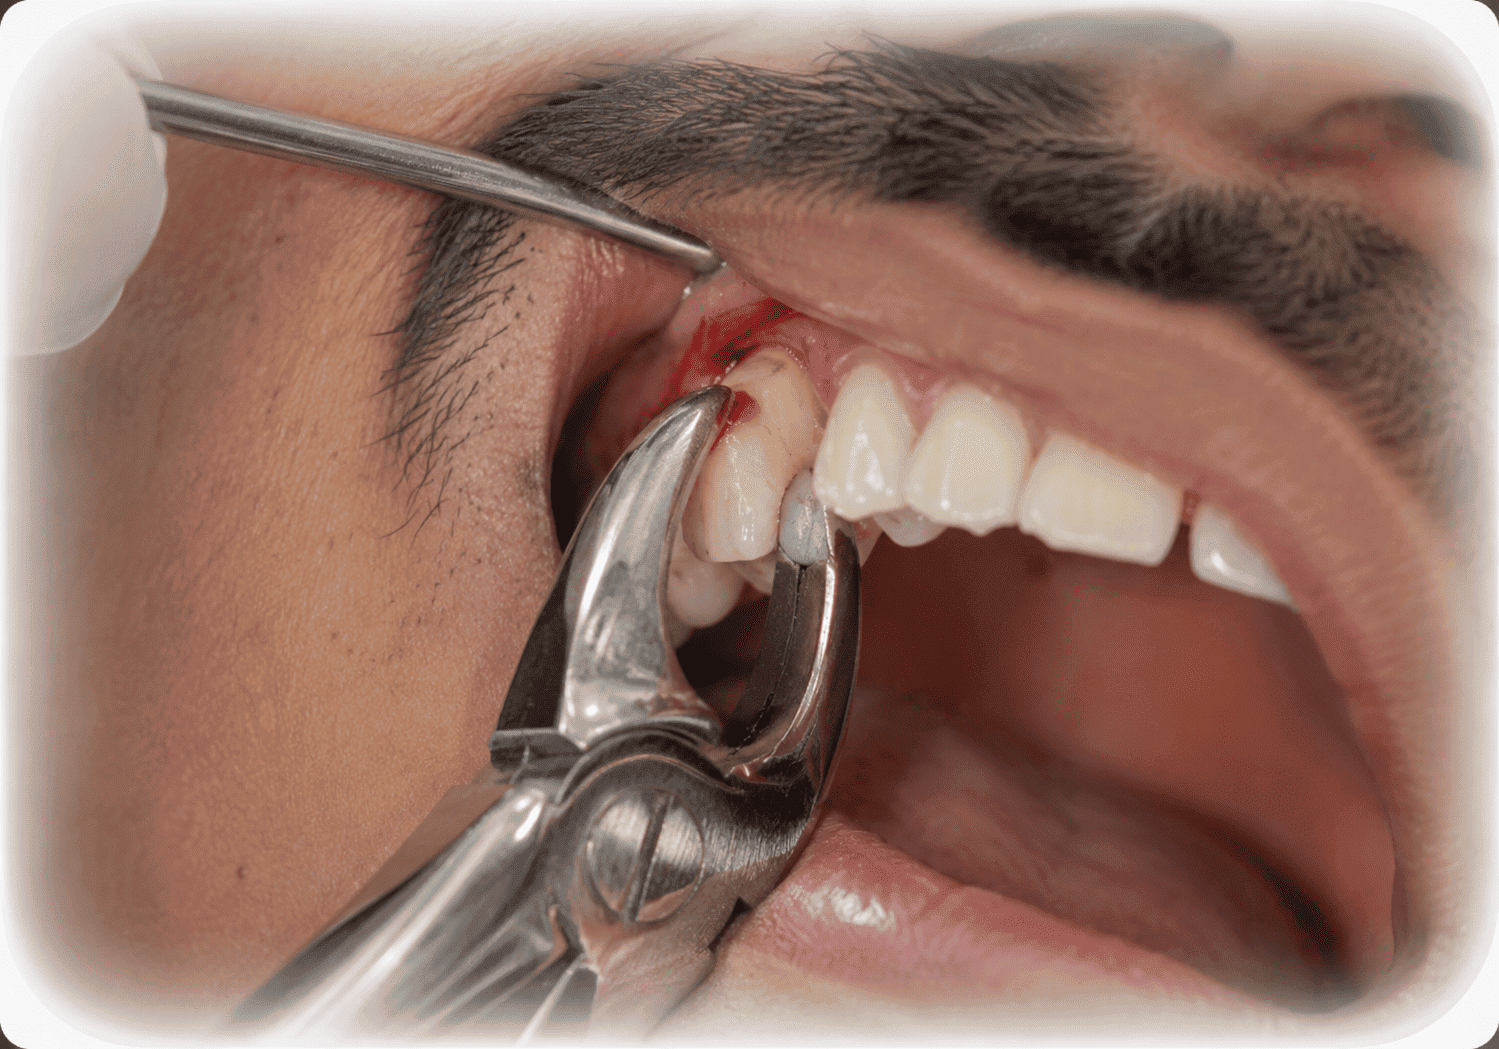

দাঁত তোলা ও সার্জিক্যাল এক্সট্রাকশন (Extraction & Surgical Extraction)